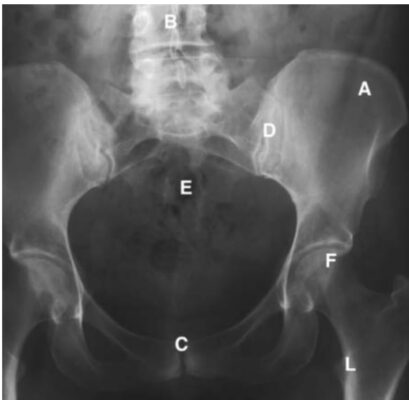

LIÊN HỆ X QUANG

Ghi chú viết tắt:

- A = Iliac crest; mào chậu

- B = Lumbar spine; cột sống thắt lưng

- C = Symphysis pubis; khớp mu

- D = Sacroiliac joint, khớp cùng-chậu

- E = Sacrum; xương cùng

- F = Femoral head; chỏm xương đùi

- G = Greater trochanter of femur; mấu chuyển lớn xương đùi

- I = Ischium; ụ ngồi

- L = Lesser trochanter of femur; mấu chuyển bé xương đùi